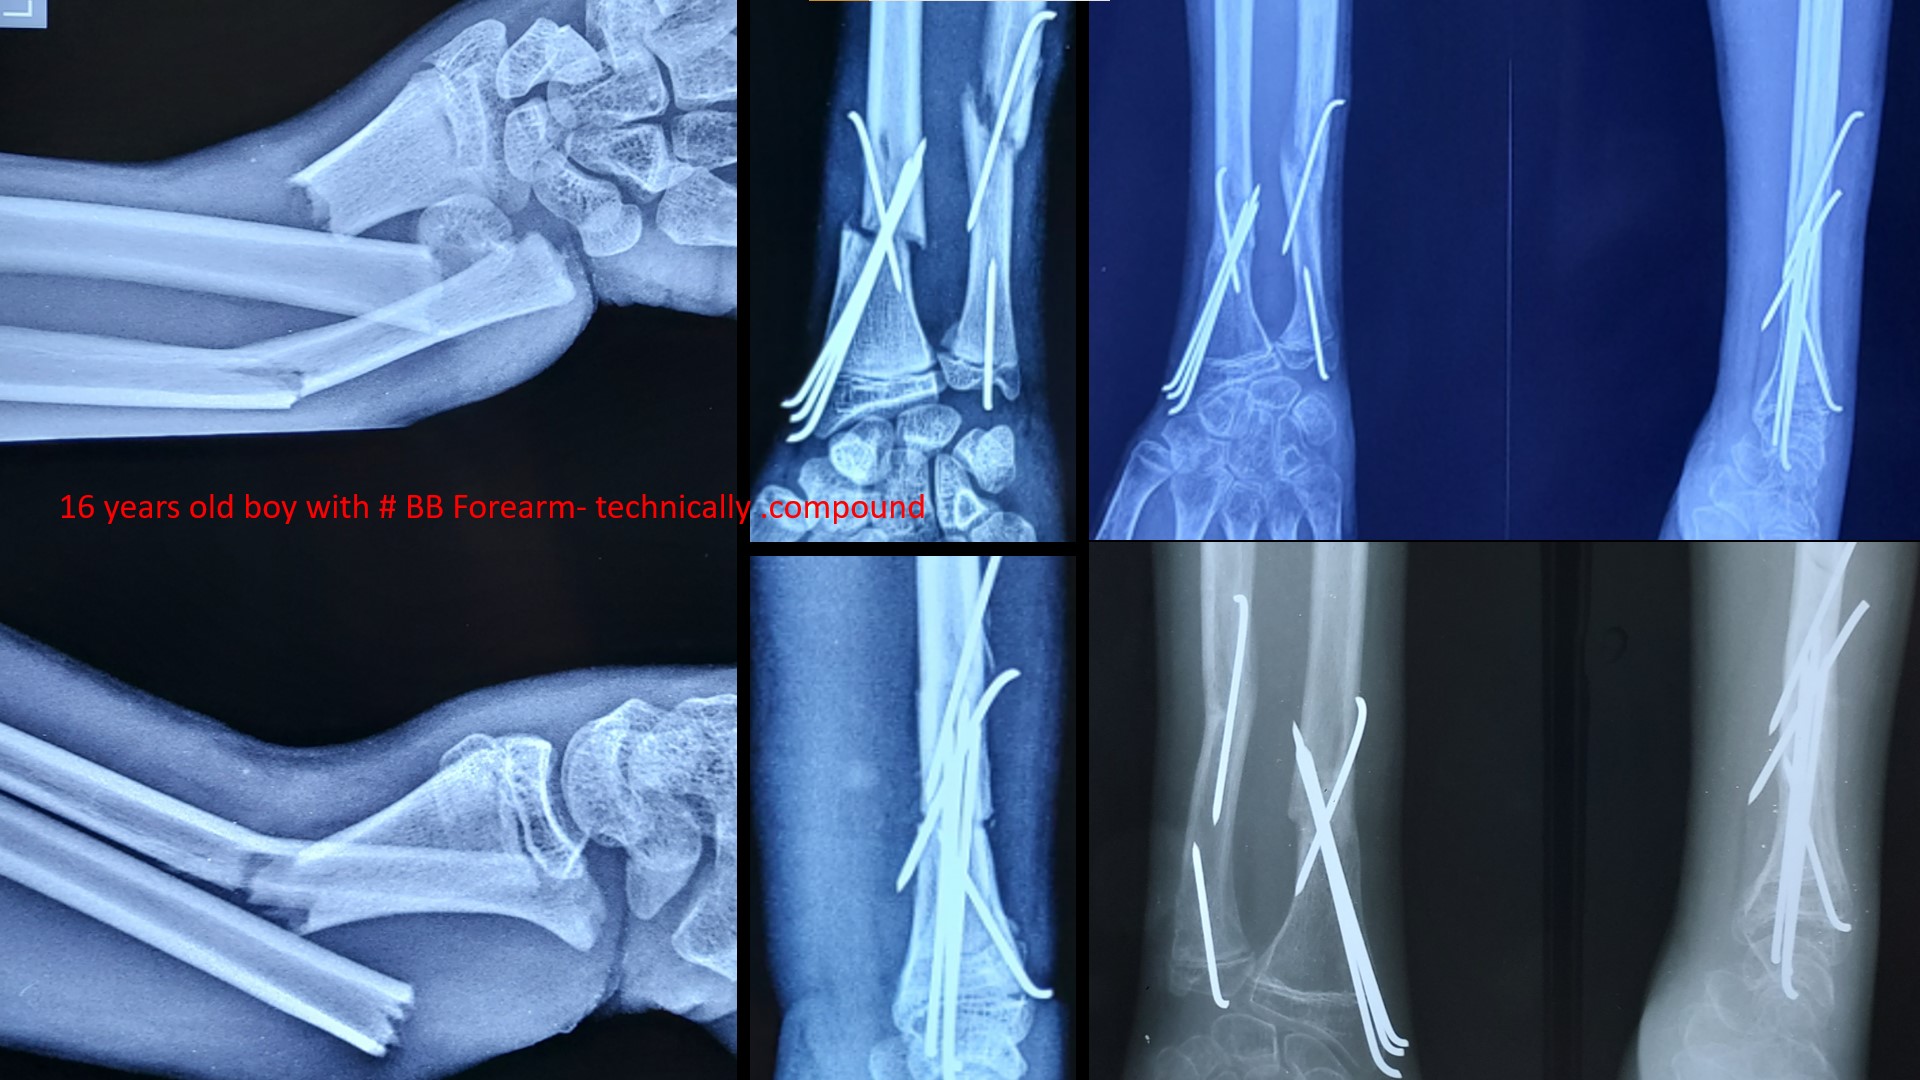

FRACTURE LOWER 3RD FOREARM